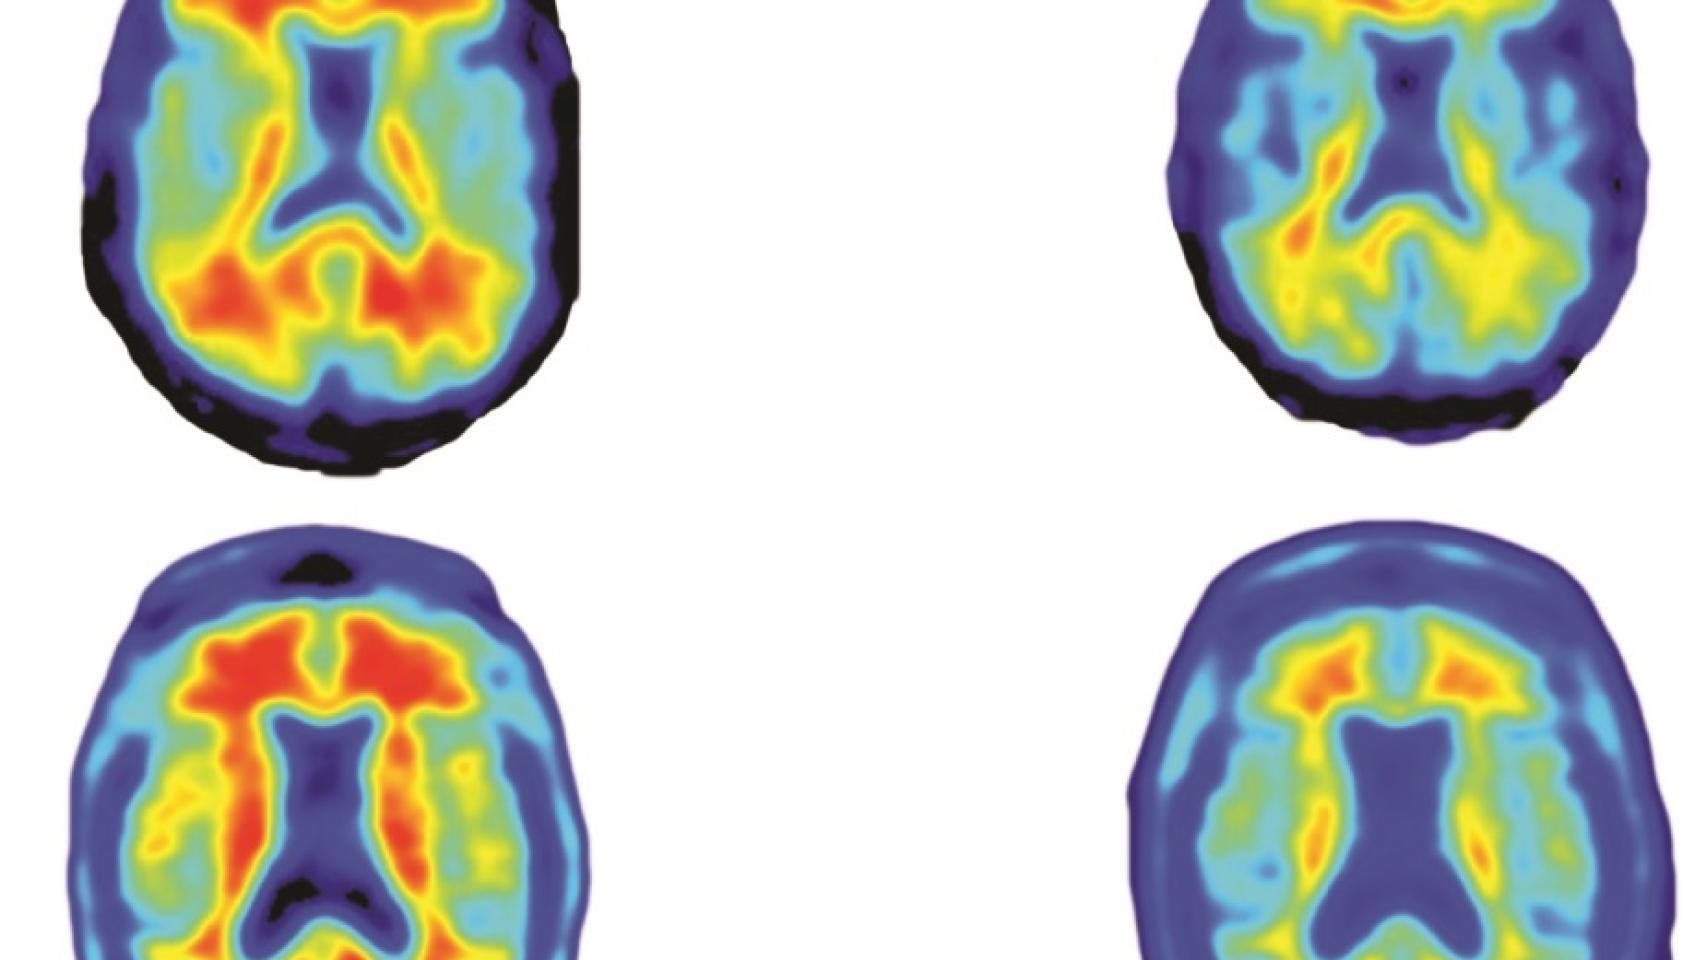

A la izquierda, cerebros sin tratar. A la derecha, tratados.

A la izquierda, cerebros sin tratar. A la derecha, tratados. Sevigny et al Nature

La acumulación de proteína beta amiloide es el desencadenante más conocido de los eventos cerebrales que llevan al alzhéimer, como se sospecha desde hace 25 años. En este cuarto de siglo no se ha conseguido evitar este fenómeno, que se visualiza fácilmente en pruebas de diagnóstico por imagen como el PET.

El estudio PRIME, que se publica esta semana pero que se presentó por primera vez el pasado año en una importante conferencia internacional sobre la enfermedad celebrada en Niza, no sólo demuestra que el fármaco reduce los depósitos de la proteína, sino que ralentiza el deterioro cognitivo asociado a esta patología. Eso es lo que realmente importa a médicos y pacientes, mucho más de los datos fríos de una prueba de diagnóstico por imagen.

Otro dato positivo es que se ha visto que la mejora va asociada a la dosis. Cuánto más medicamento recibieron los participantes asignados a tratamiento (que se dividieron en cuatro grupos según la cantidad inyectada) mayor fue la mejoría observada. De hecho, los 32 voluntarios a los que administró 10 miligramos por kilo de peso vieron sus depósitos reducidos casi a niveles previos al diagnóstico.